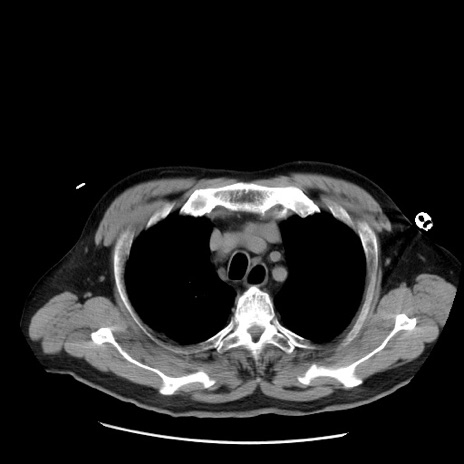

症例20(横断像)

【症例】 60歳代男性

【主訴】 腹部膨満、嘔吐

【現病歴】5日前頃より倦怠感を認め食事量減少し4日前の朝嘔吐、食事摂取困難となった。 3日前近医受診し点滴施行され整腸剤などを処方された。 当日他院を受診し、腹部膨満著明、炎症反応の上昇(CRP10.8、WBC11200)あり、紹介受診となる。

【身体所見】 意識JCS1 受け答えがはっきりしないBP 111/57mHg、 P 67bpm、、BT35.2°C、SpO2 97%(RA)、 腹部:膨隆、打診で鼓音あり、全体的に圧痛有り、腸蠕動音(-)、反跳痛ははっきりせず。

【データ】WBC 11400、CRP 14.20